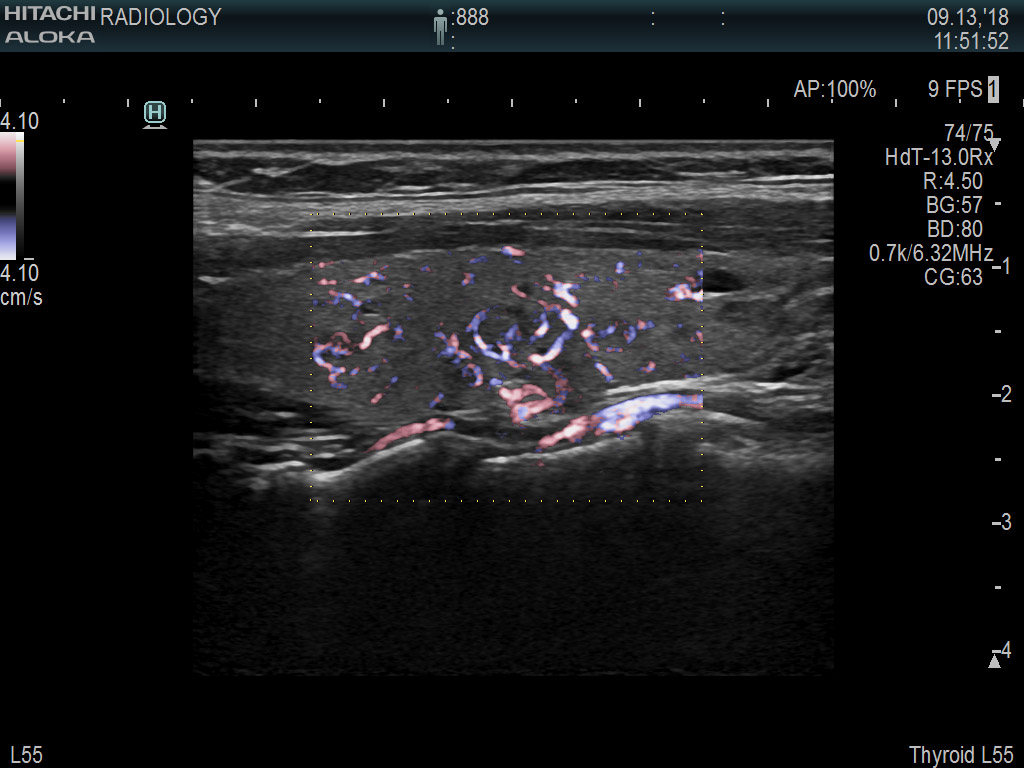

Superior guidance for all applications

Fujifilm Healthcare Americas is committed to designing tools that help surgeons navigate inside the human body and provide the necessary information to immediately make critical surgical decisions.

Fujifilm Healthcare's dedication to Surgeons provides outstanding ultrasound technology, professional support and the specialized tools necessary to best perform comprehensive real-time ultrasound imaging in Breast Surgery, General Surgery, Laparoscopic Surgery, Neurosurgery, Robotic Surgery and Surgical Oncology.